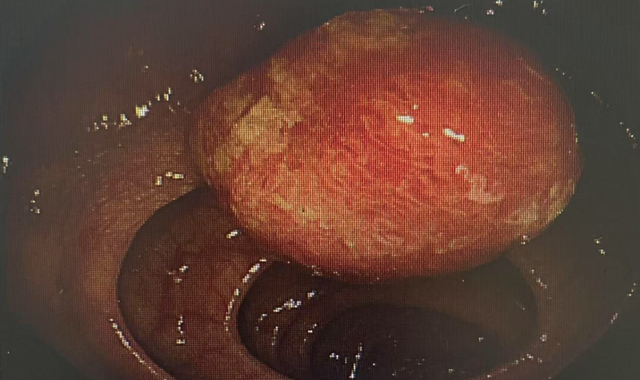

很多人往往认为,身体没有不适就等于健康。58岁的李女士(化名)也曾这样想,平时她从未感到腹部疼痛或腹胀,排便也一直正常。然而,在一次常规肠镜检查中,医生却发现她的结肠壁上分布着数枚息肉,最大直径约2厘米,小的仅如米粒大小(约0.3厘米)。这些“肠道多余物”本身可能不引起任何症状,但其潜在危险不容小觑——它们正是结直肠癌最重要的“前奏”。

结合息肉的具体情况,消化康复科团队为李女士制定了详细的内镜下切除计划。手术顺利摘除了全部息肉,过程微创且精准,在清除病变的同时尽可能保护了肠道功能,避免了出血、穿孔等风险。李女士术后恢复良好,现已恢复正常工作与生活。

病理报告显示,其中一枚较大息肉为高级别上皮内瘤变。这一病理结果具有双重重要意义:

一方面,它证实了此次内镜治疗的必要性与及时性——该病变属于癌前病变的终末阶段,是向浸润性癌发展的关键节点;另一方面,它也凸显了结肠镜筛查的极端价值,若未通过此次检查发现并处理,该病灶极有可能在数月或数年内进展为浸润性癌,届时患者将不得不接受创伤更大的外科肠段切除术,甚至需要辅助放化疗,其生活质量、治疗成本及预后都将受到严重影响。此次成功的干预,恰恰是在宝贵的“时间窗”内,以微创方式完成了一次有效的癌症预防。